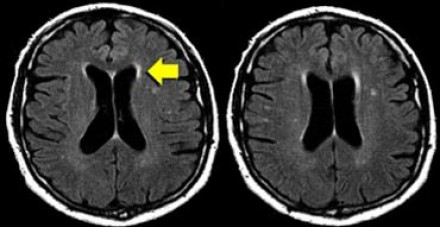

多發(fā)斑塊狀病灶的鑒別診斷

圖片一

在上圖中,是各種多發(fā)性點狀和斑塊狀白質(zhì)病灶圖像,我們對其中部分病例進行詳細討論。需要說明的是,以下鑒別診斷中提到的疾病與上圖中的圖像并不完全重合。

交界區(qū)腦梗死

MRI成像病灶要點:一般來說,這些病灶僅位于一個腦半球,要么位于深層白質(zhì)與灰質(zhì)的分水嶺區(qū)域(watershed area),要么位于周圍的分水嶺區(qū)域。在上圖中,病灶位于深層的分水嶺區(qū)域。

急性播散性腦脊髓炎(ADEM)

MRI成像病灶要點:在感染或接種疫苗后10-14天,多個局灶性病灶出現(xiàn)在腦白質(zhì)和基底節(jié)。與MS一樣,ADEM病變可累及脊髓、U形纖維以及胼胝體,有時可出現(xiàn)增強病灶。與MS所不同的是,ADEM的病灶通常更大,且好發(fā)于青年人,病程是單相的。

萊姆病

病灶大小約為2-3毫米,與MS的病灶相似,但患者會有皮疹和其他流感樣疾病。脊髓呈現(xiàn)高信號,CN7(神經(jīng)根入腦干區(qū))信號增強。

肉樣瘤

肉樣瘤的病灶分布與MS非常相似。

進行性多灶性白質(zhì)腦病(PML)

PML是一種由JC病毒感染引起的脫髓鞘性疾病,常見于免疫抑制患者。

MRI成像病灶要點:白質(zhì)損傷病灶在U形纖維的間隙占位,不增強,與HIV或CMV不同。

PML的病灶可在單側(cè)出現(xiàn),但更常見的是呈雙層、不對稱性分布。

血管周圍間隙(Virchow Robin spaces)

MRI成像病灶要點:T2加權(quán)成像明亮,F(xiàn)LAIR成像黑暗。

小血管性疾病

白質(zhì)損傷病灶位于深層白質(zhì)區(qū)域,不位于胼胝體、腦室旁或皮層旁。